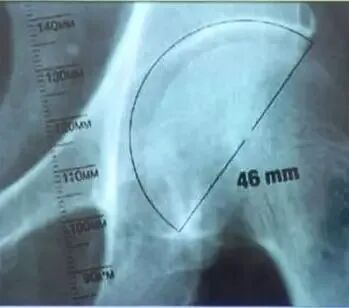

髋臼模板测量:

①选择骨盆正位片与合适比例模板;

②将模板按照45°倾斜角度放入髋臼;

③估计锉后髋臼的大小,内壁的厚度;

④假体的大小应与软骨下最少的截骨量一致;

⑤假体的中心与原髋臼的旋转中心尽可能一致。